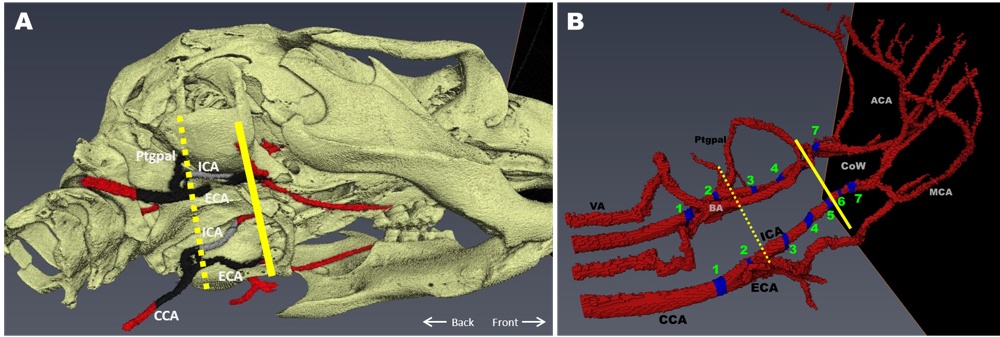

Chapter 3 Figure 1Three-dimensional reconstruction of the peripheral and cerebral arterial tree. A, CT scan showing a slightly ventrolateral view of the skull and vessels. The dashed line indicates where the atherosclerotic plaques stop in most mice. The continuous line indicates the place where the ICA enters the skull. Red indicates part of the vessels without atherosclerosis. The black indicates the part of the vessels with extensive atherosclerosis (based on 32 mice). The gray indicates atherosclerosis as observed only in one mouse. B, Magnetic resonance angiogram showing the sagittal view of the mouse arterial tree from common carotid artery (CCA) to the circle of Willis (CoW) and its main branches. The numbered blue areas indicate the areas in which immunohistochemistry sections were taken.